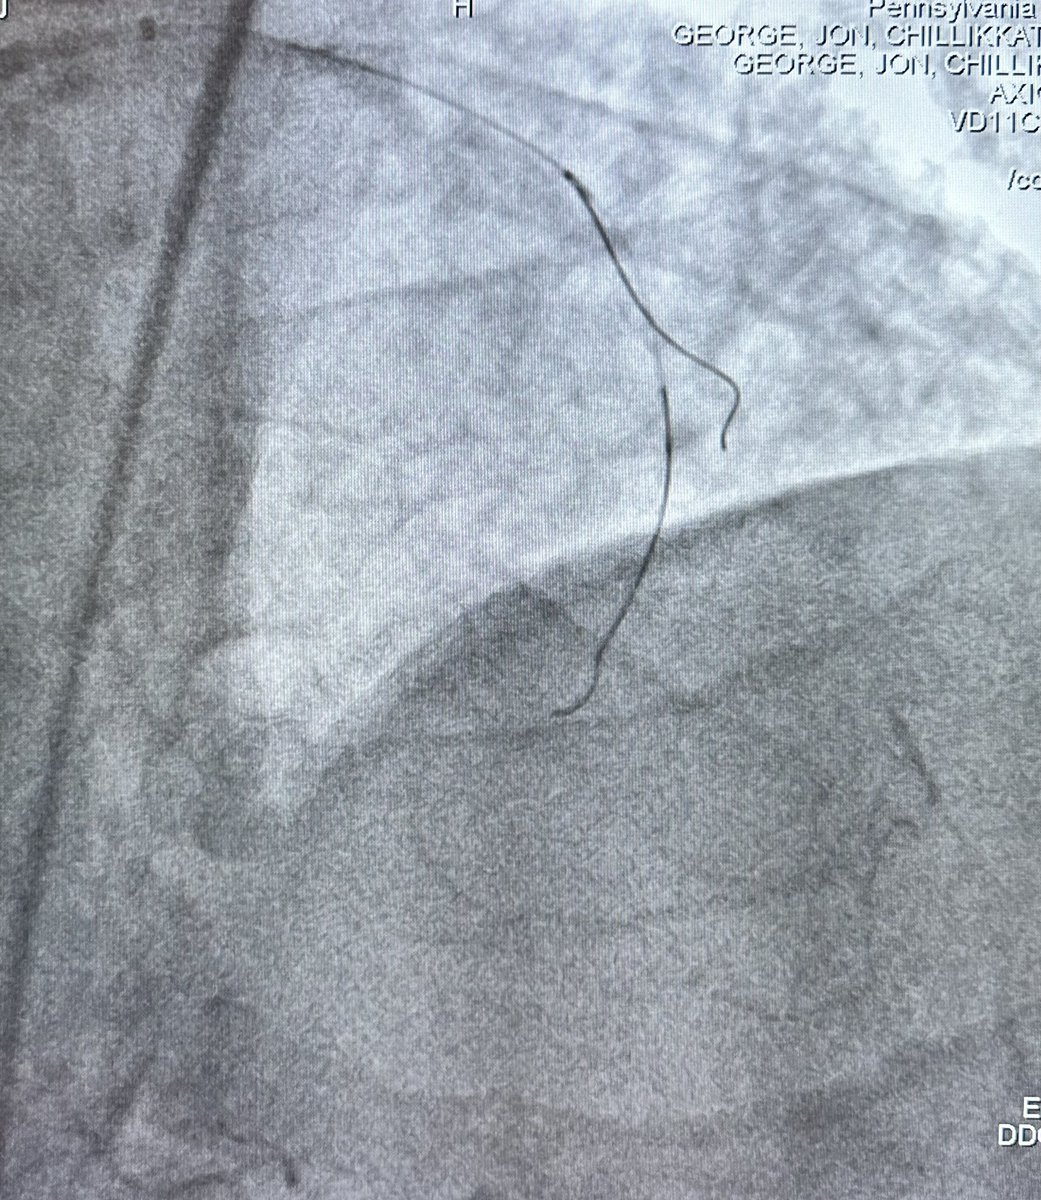

#CTOPCI at #PennsyInterventions: failed prior PCI LAD due to heavy calcification successfully crossed with initial subintimal dissection into septal and dual lumen #Sasuke catheter assisted re-entry into the true distal LAD! Combined case win with @vvarghesedo @ReVascMed